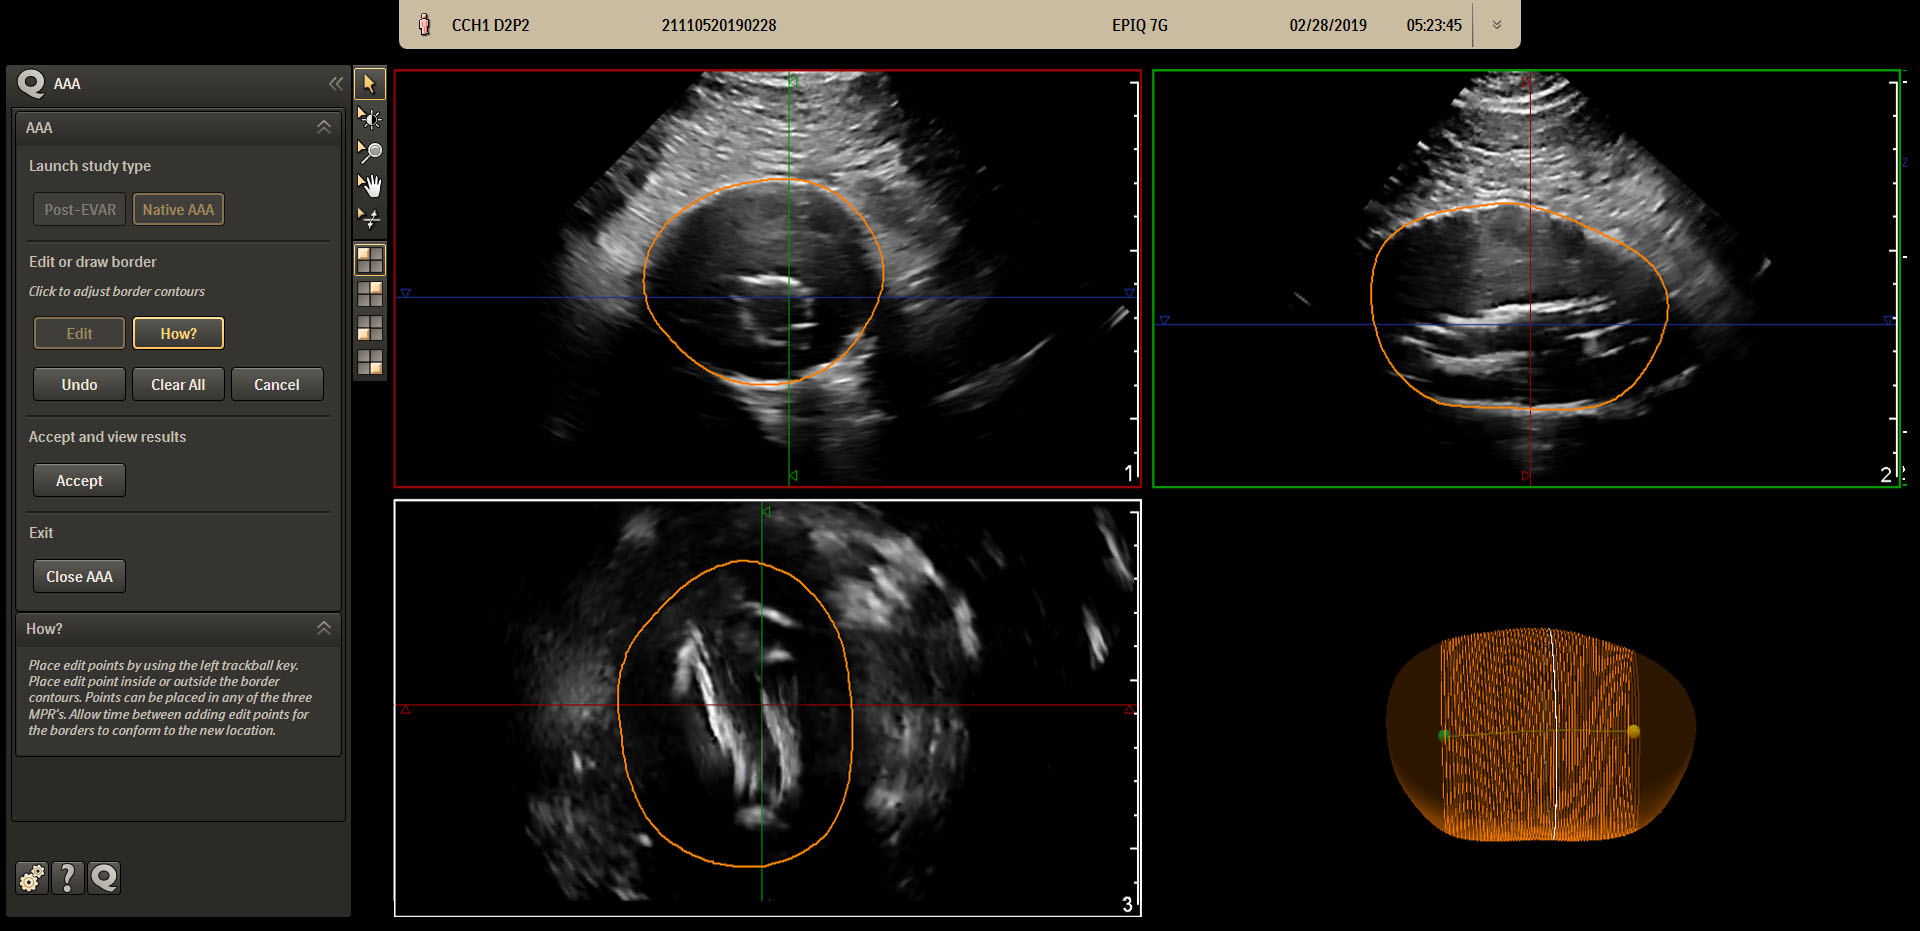

Amsterdam, the Netherlands, Jan. 27 (Korea Bizwire) – Royal Philips (NYSE: PHG, AEX: PHIA), a global leader in health technology, has introduced the Philips Abdominal Aortic Aneurysm (AAA) Model, providing physicians a more patient-friendly solution compared to the current standard of care for managing AAA patients. Based on 3D ultrasound, Philips AAA Model delivers clinicians accurate diagnostic information without exposing patients to high doses of radiation and nephrotoxic contrast agents.

An abdominal aortic aneurysm (AAA) is an aneurysm that forms in the lower part of the aorta. Typically, AAAs are identified incidentally during abdominal imaging exams but, in some cases, remain undetected until rupture. A ruptured AAA has an 80% mortality rate [1], emphasizing the importance of routine surveillance. Philips AAA Model integrates innovative software and leading Philips 3D ultrasound technologies into a single solution to help increase diagnostic confidence and an improved patient experience. The software automatically segments and quantifies the size of the aneurysm sac for surveillance of known native (untreated), and post-EVAR (treated) AAAs.

The current standard of care for AAAs includes 2D ultrasound and computed tomography angiography (CTA). Each of these modalities has its drawbacks, including inter-operator variability with 2D ultrasound and patient exposure to high levels of radiation and nephrotoxic contrast agents with CTA.

A recent clinical study showed that 3D ultrasound examination for native AAA surveillance has excellent inter-operator reproducibility, superior to that of 2D ultrasound, supporting the broader use of 3D ultrasound in standard AAA surveillance programs [2]. 3D ultrasound has been shown to estimate the diameter and volume of an AAA with acceptable reproducibility and an improved agreement (over 2D ultrasound) with CT [3]. Furthermore, 3D ultrasound has also been proven to correlate significantly better to 3D CT than 2D ultrasound for assessing the maximum diameter of the residual sac post-EVAR, with clinically acceptable reproducibility [4].